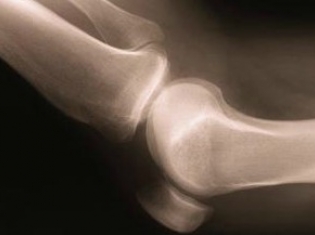

Bisphospohonates are drugs that are designed to boost bone density and prevent fractures for people with osteoporosis. But for about 1 in 1,000 patients who have taken the drugs over a long period of time, they cause fractures in unusual places, such as the femur.

New research presented at the 2012 Annual Meeting of the American Academy of Orthopaedic Surgeons finds that stopping use of these bone boosting drugs after a patient suffers an atypical fracture can lower a patient's risk for another painful break.

They found that 41.2 percent of patients who continued use of the drug for three or more years after an atypical fracture experienced another fracture in their other thigh bone, compared to 19.3 percent incidence for patients who discontinued bisphosophonate use after their first fracture.

The risk of another fracture was decreased by 53 percent if the patients stopped taking the drugs after the first fracture, the researchers discovered.

Based on these findings, Dr. Dell recommends discontinuing bisphosphonate use as soon as possible after the first fracture, monitoring these patients through X-ray or MRI, and finding an alternative osteoporosis medication.